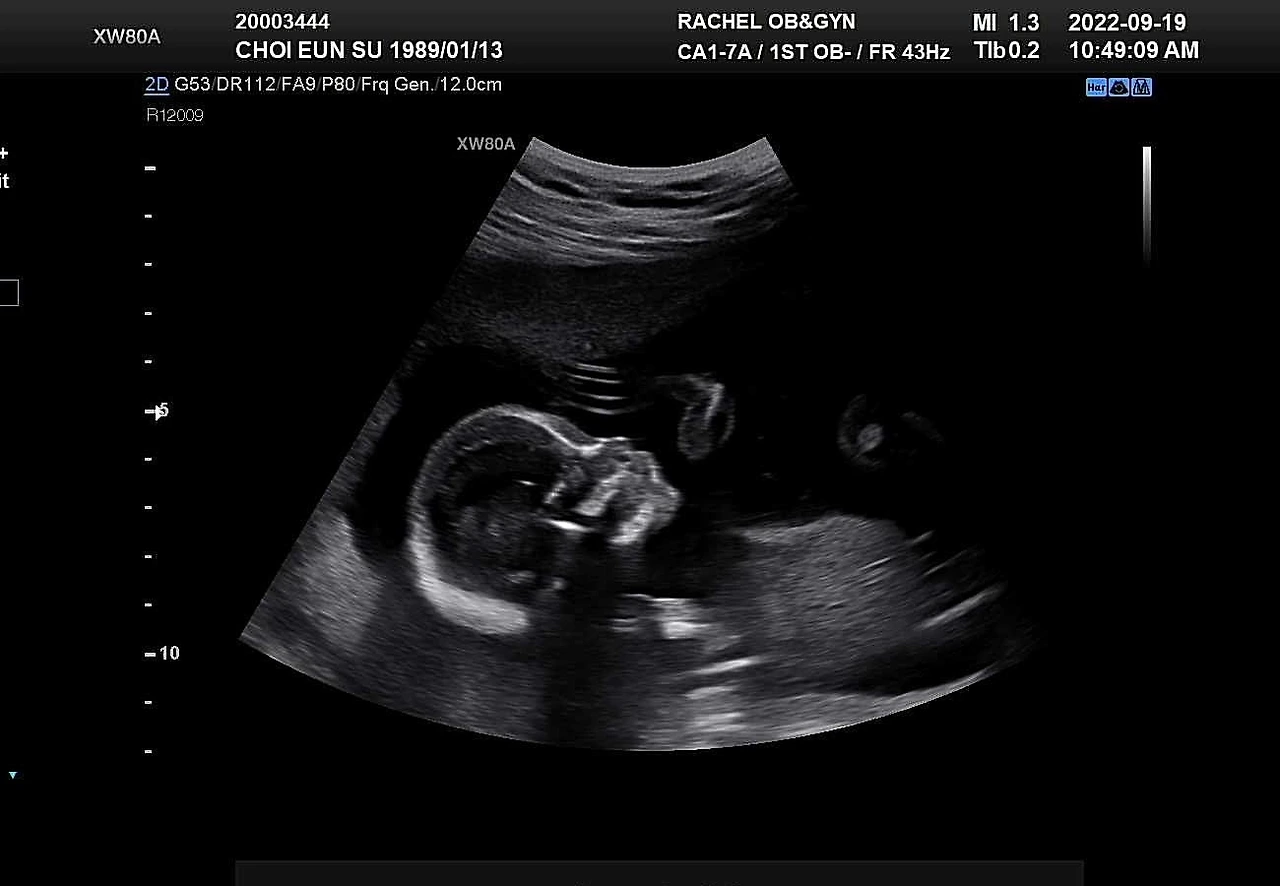

17주차 초음파 사진

아기크기 12cm. 기형아검사 결과 청취와 난임병원 졸업.